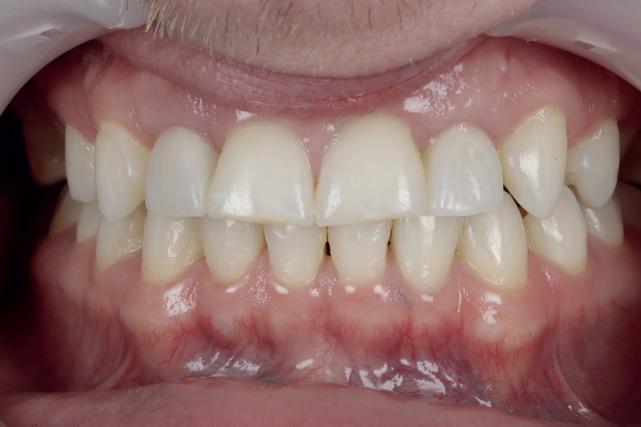

CASE STUDY

Guided implant approach for reproducible results, page 28